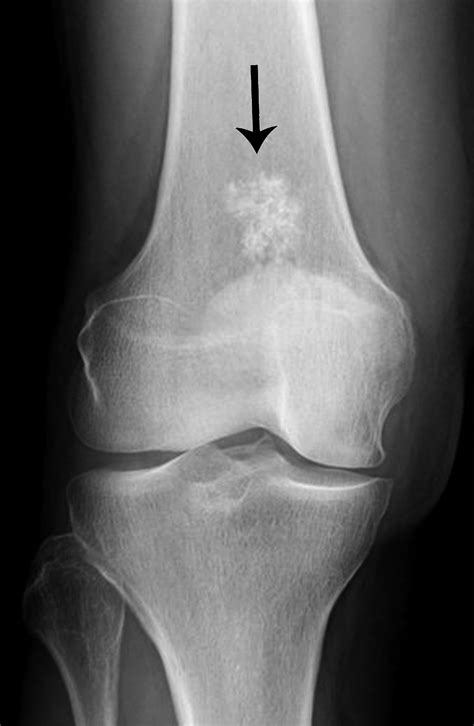

Bony lesions refer to any abnormal growths, defects, or changes in the bone tissue. These lesions can be benign (non-cancerous) or malignant (cancerous) and can occur in any part of the skeletal system. They are often detected through imaging techniques such as X-rays, CT scans, MRI, or bone scans. The characteristics of bony lesions can vary widely, making accurate diagnosis essential for appropriate treatment.

• Imaging Studies: X-rays, CT scans, MRI, and bone scans are commonly used to visualize the lesion and determine its characteristics.